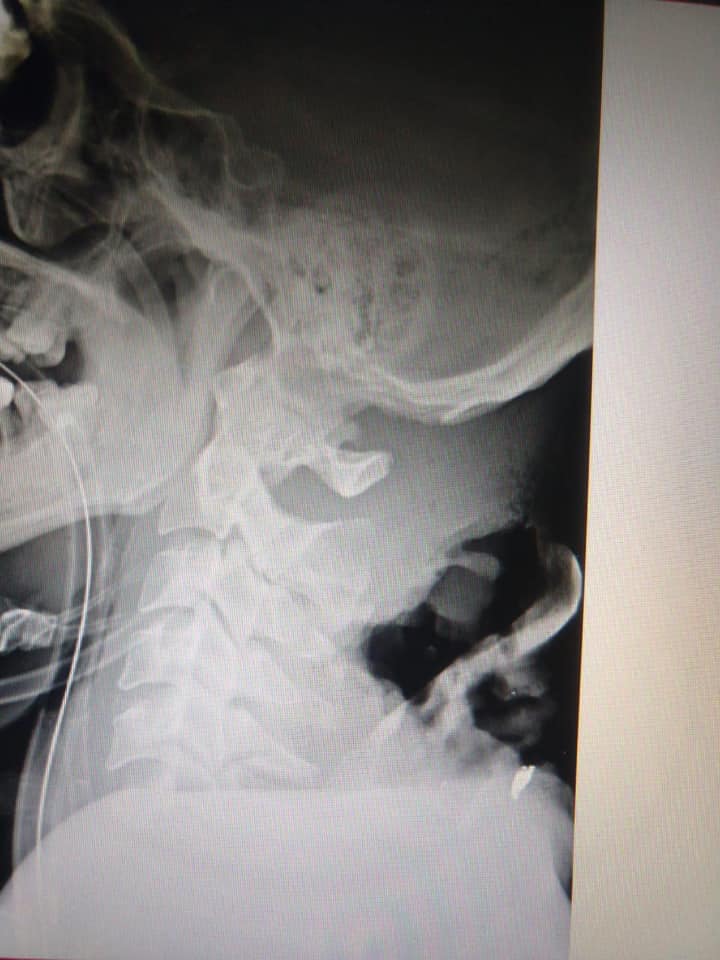

На фото - Співак Назар Назар Спивак. Йому 32 роки, він родом з міста Ходорів, Львівської області. Доброволець 8 батальйону УДА «Аратта». Поранений тиждень тому. У нього складне поранення в шию, з пошкодженням шийного відділу хребта (повний параліч рук та корпусу, частковий параліч ніг). На даний момент він знаходиться в реанімації та його стан важкий, але уже на щастя можна сказати стабільний. Уже зараз потрібно готуватись до тривалої реабілітації та великої кількості медичних та гігієнічних засобів на перший час.Що ми можемо зробити? Зробити внесок в порятунок Героя та його подальшу реабілітацію та якісне самостійне життя